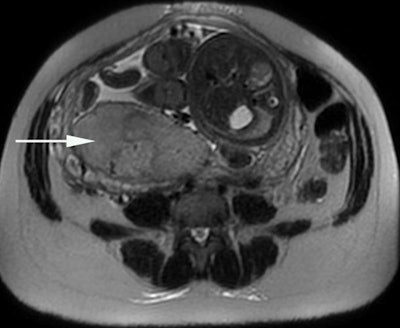

Historically, placental MRI was seen as a complementary problem-solving tool for placental evaluation, and it was much less common than fetal MRI, Siauve explained. However, placental abnormalities are of considerable clinical significance, due to their association with high rates of fetal morbidity and mortality, and placenta previa, placental adherence abnormalities, and placental insufficiency are key defects here.

"MRI has recognized added value for the management of placental adherence abnormalities, which requires a multidisciplinary team approach," she continued. "The early detection of placental adherence abnormalities is of crucial importance for determining the most appropriate surgical management technique and preventing hemorrhage during the delivery."

"Intensity heterogeneity is an emerging MRI marker of placental invasion. However, the reading of the images is subjective and this heterogeneity is difficult for human readers to quantify," she stated. "Texture analysis could be used for quantitative image analysis to assess placental heterogeneity. Machine-learning analysis with MRI-derived texture analysis features is a potentially feasible tool for the identification of placental tissue abnormalities underlying placental adherence abnormalities."